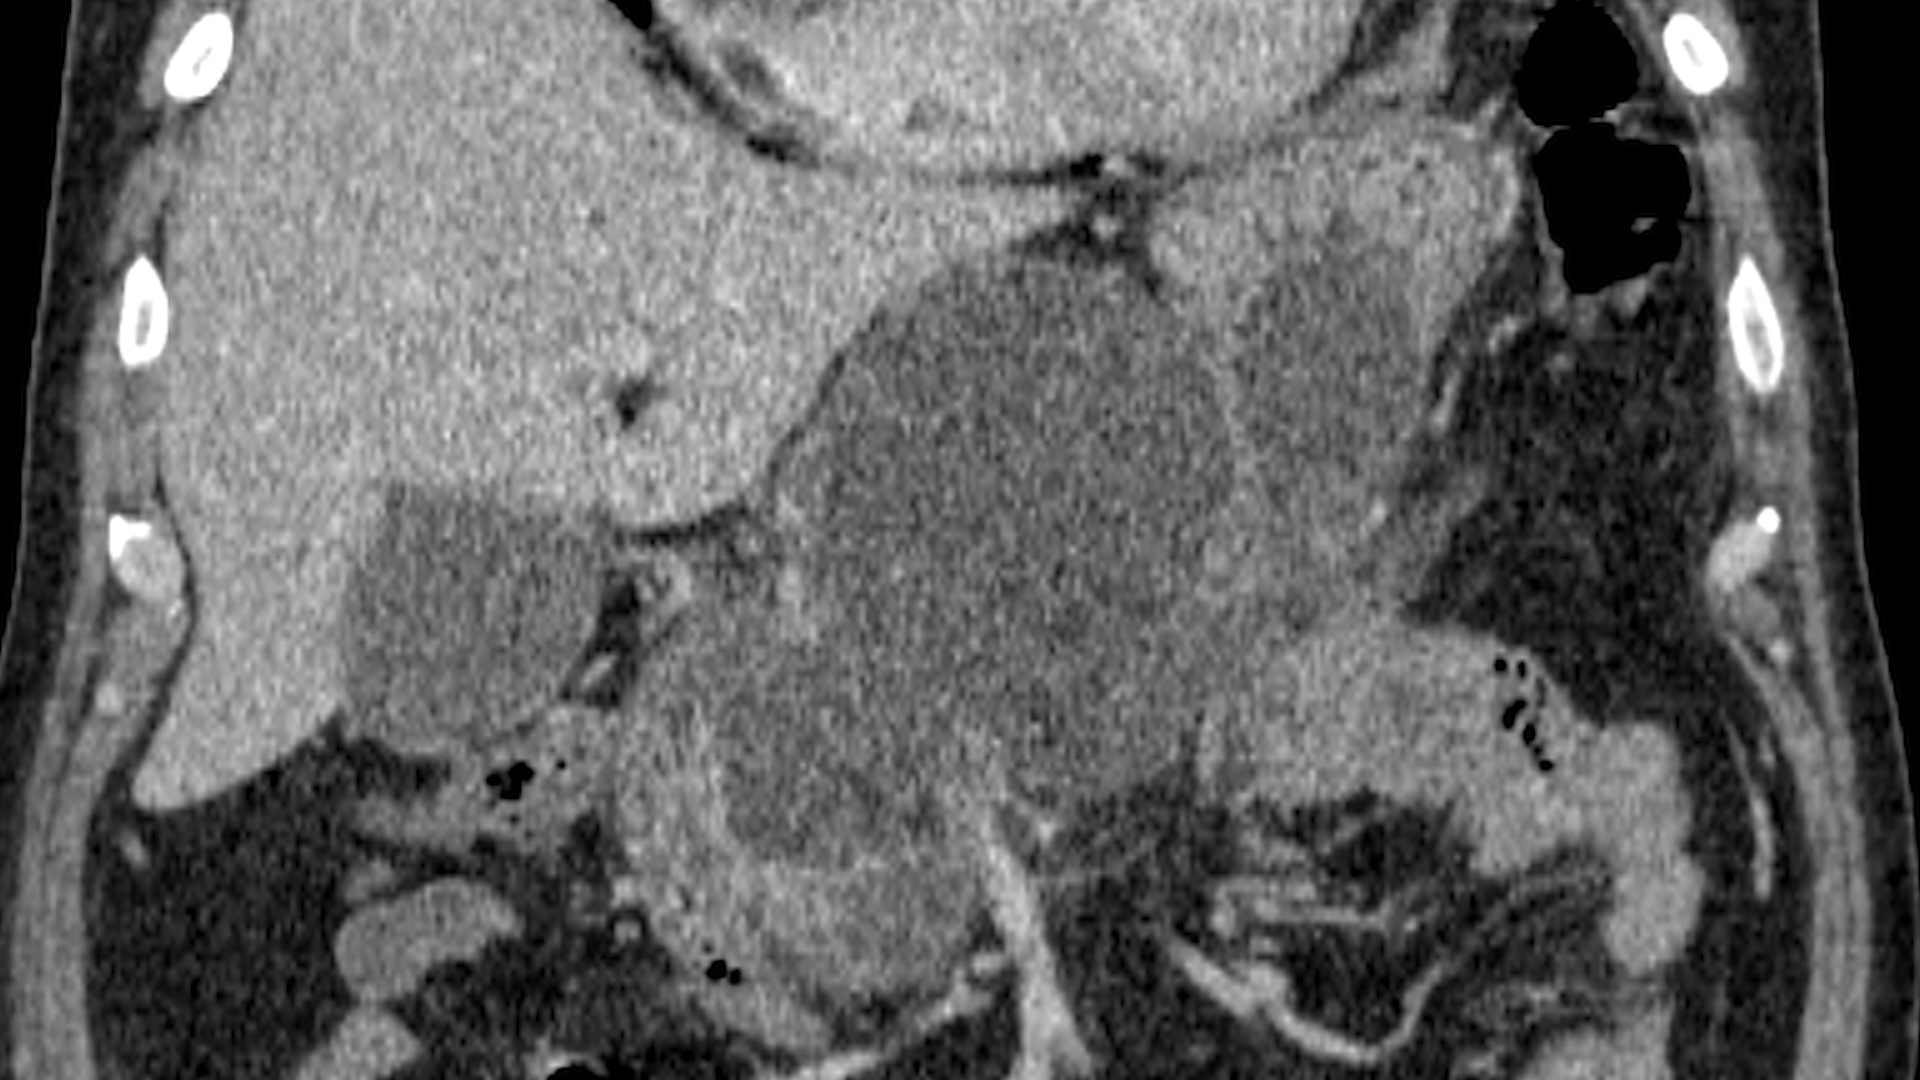

Bărbat în vârstă de 53 ani, fumător, cu un episod de pancreatită acută formă severă, de etiologie incertă, complicat cu o colecție pancreatică gigantă, compresivă la nivel gastric, cu necroze în interior (de tip walled-off pancreatic necrosis) (Fig. 1-3).

RMN identifică colecție peripancreatică de 12/6/7 cm la nivel cefalo-pancreatic, cu material necrotic în interior.

Examinarea ecoendoscopică evidențiază colecție peripancreatică de mari dimensiuni (12/7/6 cm) cu zone hiperecogene declive, cu aspect sugestiv pentru necroză (Film 1). S-a efectuat puncție ghidată EUS cu ac FNA 19G și s-a aspirat lichid brun. Ulterior, sub ghidaj EUS și ghidaj radiologic, s-a montat transgastric stent tip LAMS (HotAXIOS, Boston Scientific) 15 mm pe fir ghid 0,035 Fr, cu drenajul a cca. 1000 mL lichid brun (Fig. 3-4). Ulterior s-a introdus un stent dublu pigtail prin stentul metalic LAMS (Fig. 5).